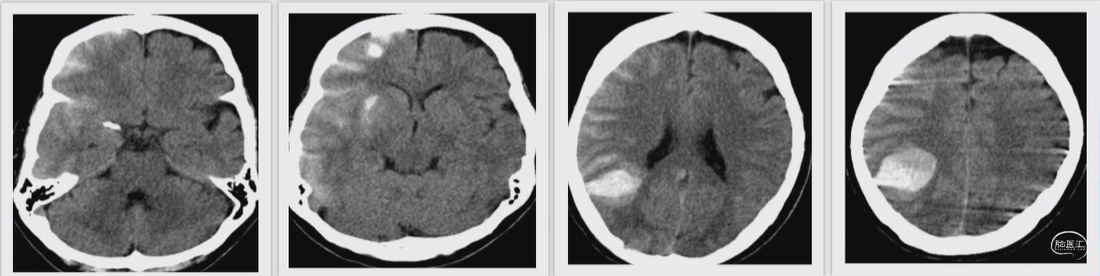

病例示例04:

女性,66岁。术后再灌注出血。

杨XX,66岁,女性。

间断性头晕伴四肢感觉麻木1年余。

左上肢曾一过性乏力,自觉左下肢感觉麻木症状较对侧严重

2020年6月诊断为多发性骨髓瘤;因骨质疏松导致腰椎压缩性骨折,曾行椎体成形术

神志清,视力视野无异常,四肢肌力5级,肌张力正常。NIHSS 1分,mRS1分。

入院诊断:双侧大脑中动脉狭窄,多发性脑梗塞,多发性骨髓瘤,脑动脉硬化。

术后6小时CT:

右侧顶叶、基底节区与右侧额顶颞叶脑沟及外侧裂池高密度影,首先考虑对比剂外渗,未排合并出血

术后第一天24小时CT:

右侧顶叶、基底节区与右侧额顶颞叶脑沟及外侧裂池高密度影,考虑为出血

术后第15天,来院门诊复诊CT

神志清,精神状态好,GCS 15分,肌力肌张力正常。